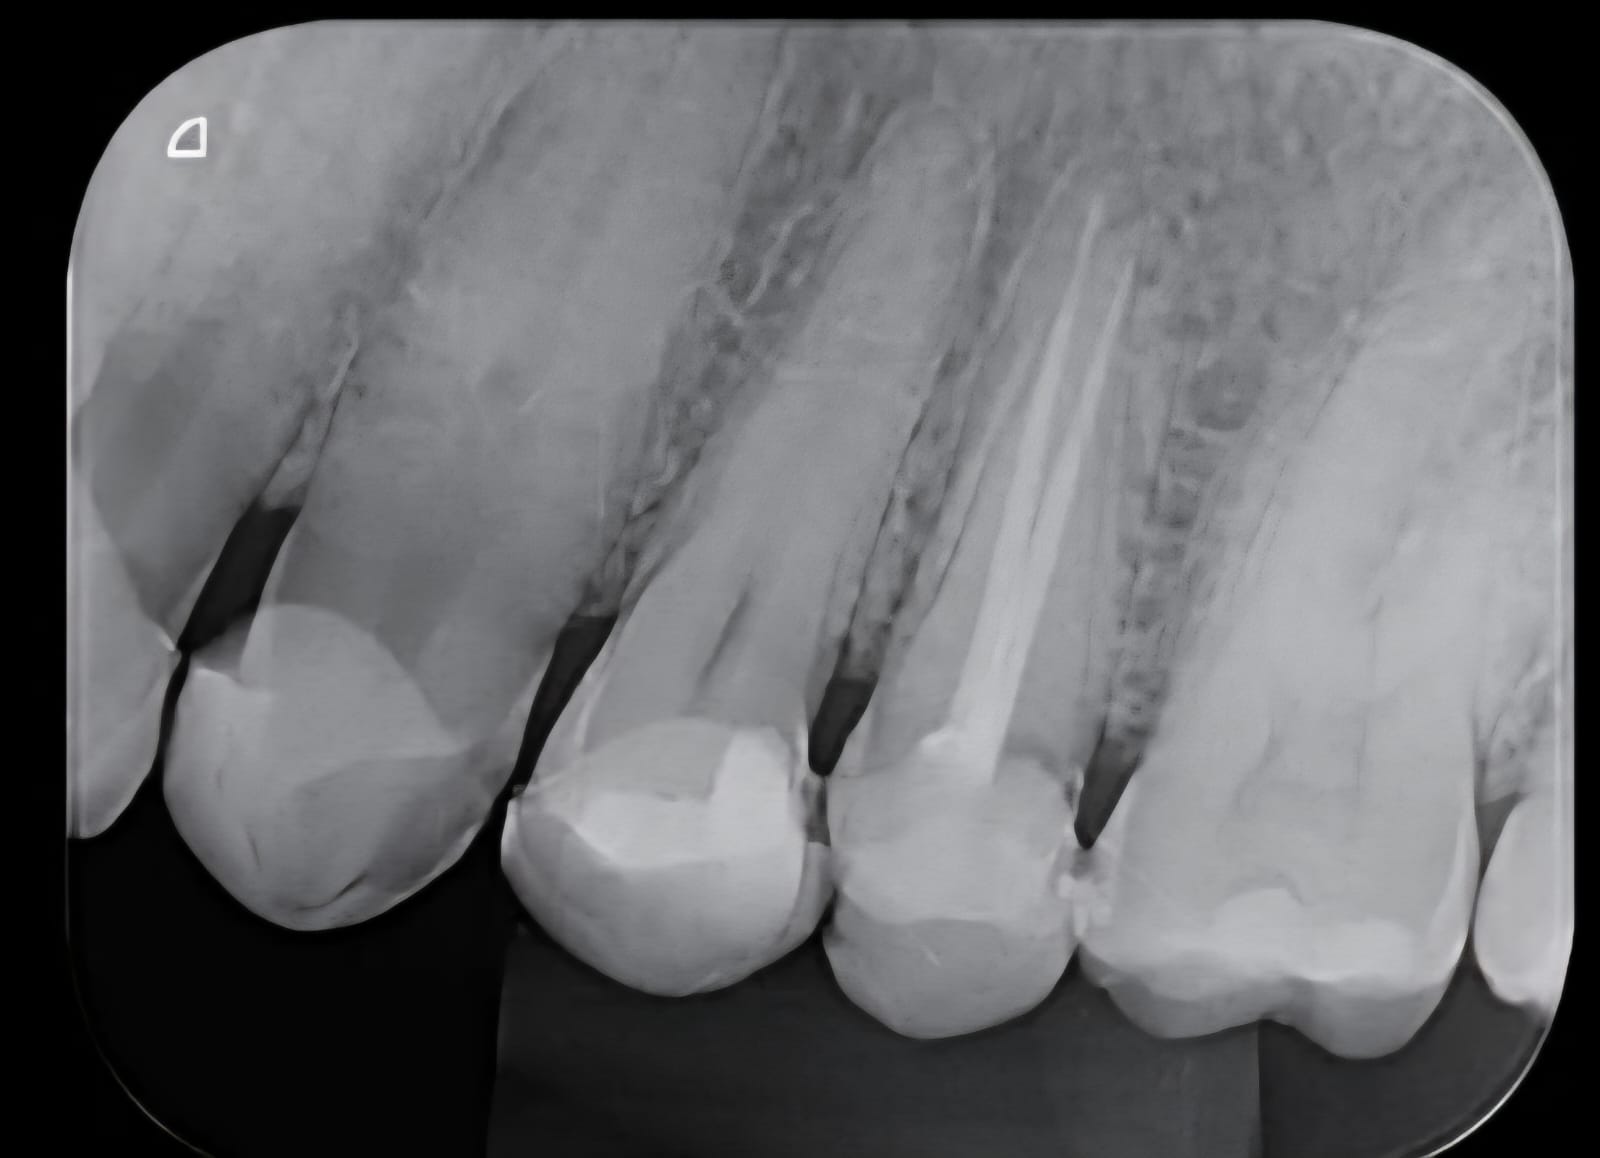

Endodontia moderna com a Dra. Flávia Rebecca. Técnicas minimamente invasivas que salvam seus dentes naturais com procedimentos precisos e confortáveis.

Profissional em tratamento de canal com técnicas modernas e minimamente invasivas. Comprometida em salvar dentes naturais com procedimentos precisos e confortáveis.

O tratamento de canal geralmente é realizado em 1 a 3 sessões, dependendo da complexidade do caso. Cada sessão dura em média 1 hora.